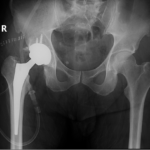

Surgical Procedure

The surgery is performed under general anesthesia. During the procedure a surgical cut is made over the hip to expose the hip joint and the femur is dislocated from the acetabulum. The surface of the socket is cleaned and the damaged or arthritic bone is removed using a reamer. The acetabular component is inserted into the socket using screws or occasionally bone cement. A liner made of plastic, ceramic or metal is placed inside the acetabular component. The femur or thigh bone is then prepared by removing the arthritic bone using special instruments, to exactly fit the new metal femoral component. The femoral component is then inserted to the femur either by a press fit or using bone cement. Then the femoral head component made of metal or ceramic is placed on the femoral stem. All the new parts are secured in place using special cement. The muscles and tendons around the new joint are repaired and the incision is closed.